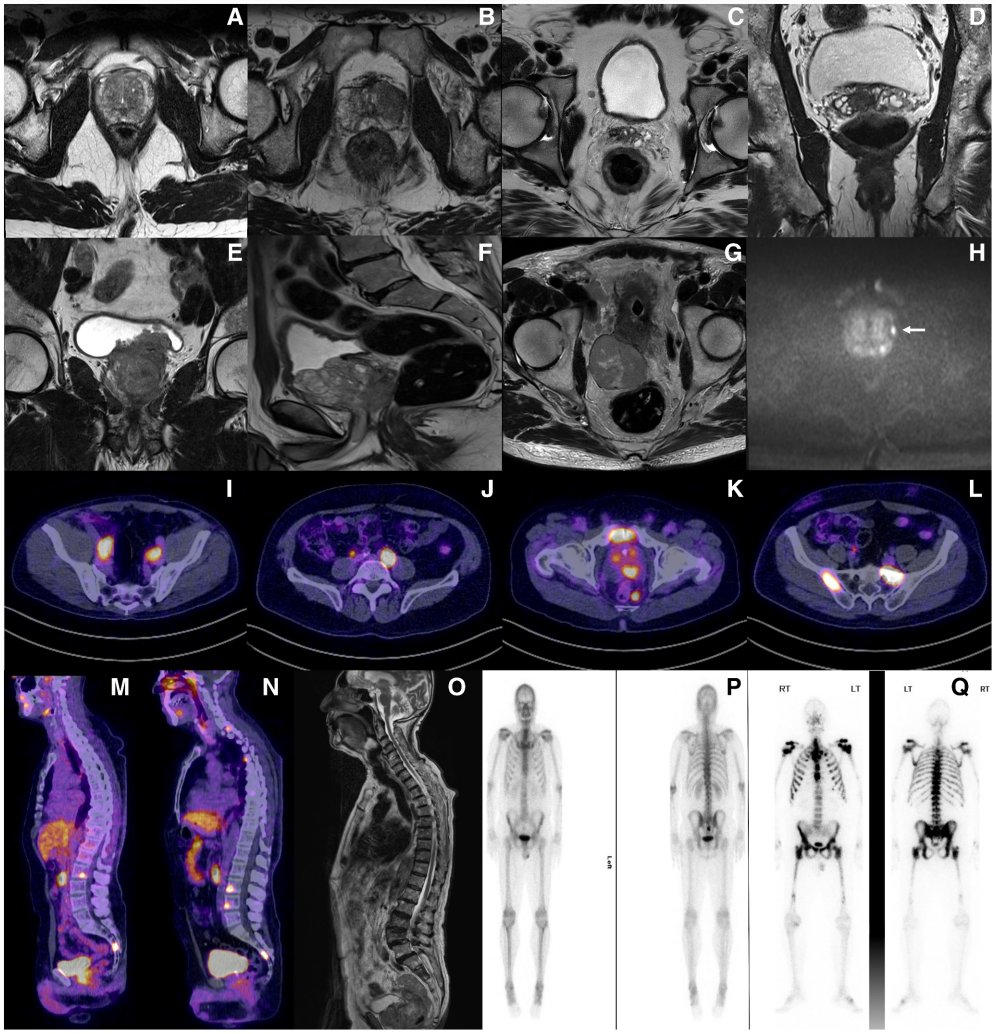

- 先进影像技术:多参数磁共振成像(mpMRI)能够清晰地识别出前列腺内的可疑病灶,指导医生进行靶向活检,显著提高活检的阳性率。而对于高危或疑似转移的患者,PSMA-PET/CT扫描在定位淋巴结及远处转移灶方面,其灵敏度和特异性远超传统影像学检查。